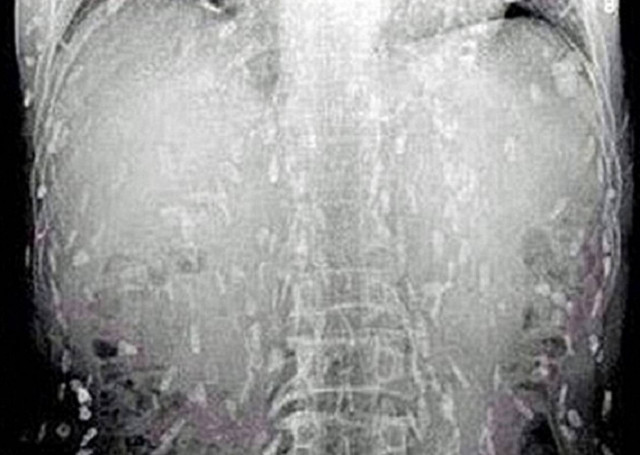

Κίνα: Έφαγε χαλασμένο σούσι και γέμισε το σώμα του παράσιτα! (pics)

ΚΟΣΜΟΣ · 25.09.2014 - 23:15

Τη ζωή λίγο έλειψε να στοιχίσει σε έναν Κινέζο η αγάπη του για το σούσι!